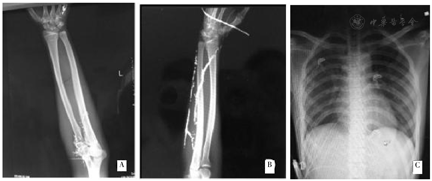

辅助检查:动脉血气分析FiO2吸氧浓度(21%):pH 7.40,氧分压(PaO2)93 mmHg,二氧化碳分压(PaCO2)40 mmHg,碳酸氢盐(HCO3-)24.8 mmol/L,碱剩余(BE)0 mmol/L,氧饱和度(SaO2)97%,K+ 3.8 mmol/L,Na+ 141 mmol/L,血糖(Glu)5.8 mmol/L,乳酸(Lac)0.5 mmol/L。血常规:白细胞12.75×109/L,血小板118×109/L,淋巴细胞百分比7.2%,中性粒细胞百分比85.5%,红细胞4.66×1012/L,红细胞压积42.7%。生化指标:谷丙转氨酶17 U/L,谷草转氨酶17 U/L,γ-谷氨酰转肽酶10 U/L,尿素氮2.9 mmol/L,肌酐72 μmol/L,总胆红素19.2 μmol/L,总蛋白62.1 g/L。尿常规:比重1.004,尿蛋白、尿葡萄糖、尿酮体、尿胆红素均为阴性,白细胞、细菌数正常。双上肢X线显示患者左肘部、左手背第5掌骨及右前臂金属汞沉积,呈树枝状分布(图2A、图2B);胸部X线未见肺内金属样密度影沉积(图2C)。

A:左上肢;B:右上肢;C:胸部